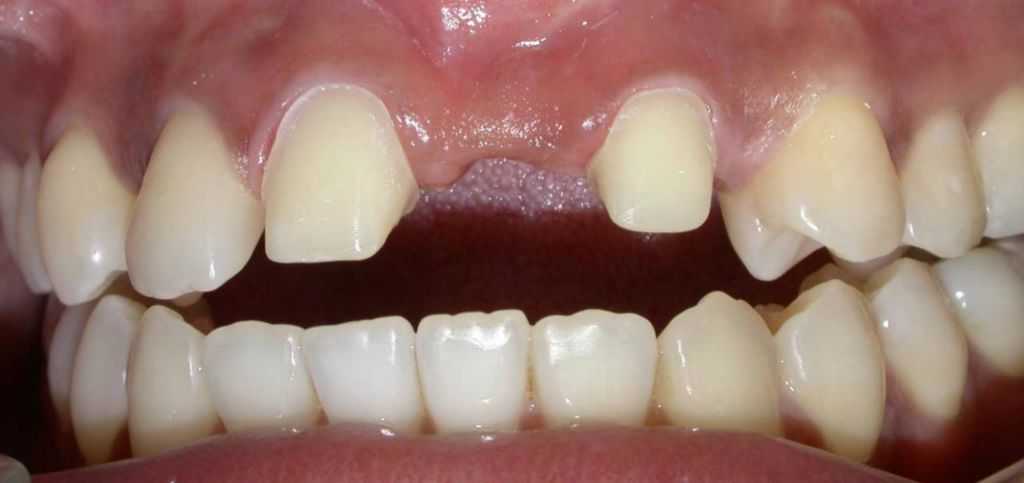

Before

After